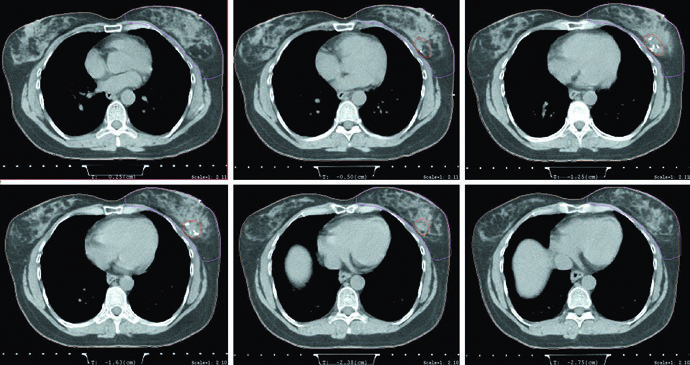

Tomografia de simulação, posição supina, prona e DIBH

Na simulação para mama inteira, o capítulo recomenda tomografia com espessura de corte menor ou igual a 3 mm, em posição supina ou prona. Para APBI, a exigência fica mais estreita: cortes de 1,5 a 2 mm através da cavidade de lumpectomia podem melhorar a definição desse volume. Não é um detalhe burocrático. É a diferença entre aceitar uma cavidade apenas presumida e enxergar melhor o alvo que depois orientará a expansão de CTV e PTV.

Quando a opção é pelo setup supino, a paciente deve ficar em prancha mamária com os braços acima da cabeça. Se o tumor é à esquerda, o texto recomenda considerar respiração profunda em inspiração mantida, a técnica de DIBH, para reduzir a dose no coração. O verbo usado importa. O capítulo não transforma DIBH em ritual obrigatório para todos os casos à esquerda, mas deixa claro que a redução da dose cardíaca deve entrar no raciocínio do planejador sempre que esse recurso estiver disponível e for reproduzível.

A posição prona ganha um espaço amplo e bem delimitado. Pacientes com mamas pendulares podem se beneficiar dela porque a separação diminui e a homogeneidade do tecido no planejamento melhora, algo que pode reduzir toxicidade aguda. O texto ainda aponta duas consequências dosimétricas: menos radiação no pulmão e possibilidade de evitar melhor o coração. Só que os autores fazem a ressalva que interessa à prática: se o leito tumoral encosta na parede torácica, o coração pode paradoxalmente se aproximar do campo de tratamento. O capítulo não vende a prona como solução automática; ele a apresenta como ferramenta útil, desde que o caso seja lido com cuidado.

Há também disciplina mecânica no setup prono. A paciente deve ser colocada em uma prancha dedicada para mama, e o conforto precisa ser garantido porque a reprodutibilidade depende disso. O texto fecha esse bloco lembrando que lesões ortopédicas no dorso ou no pescoço podem tornar a prona uma má escolha. É um ponto simples, mas clínico. O melhor arranjo geométrico perde valor se a paciente não consegue reproduzi-lo ao longo do tratamento.

Essa comparação entre supino e prono conversa diretamente com o planejamento das figuras. O exemplo em prono usa tangentes com field-in-field, a mesma prescrição de 42,4 Gy em 2,65 Gy por fração e boost com mini-tangentes fotônicos até 10 Gy em 2,5 Gy por fração. A legenda ainda acrescenta um detalhe anatômico que serve de guia: a borda posterior do campo deve incluir parte do músculo peitoral. Para quem quiser avançar do raciocínio da mama inicial para cobertura regional, vale continuar a leitura no nosso artigo sobre irradiação nodal regional no câncer de mama.